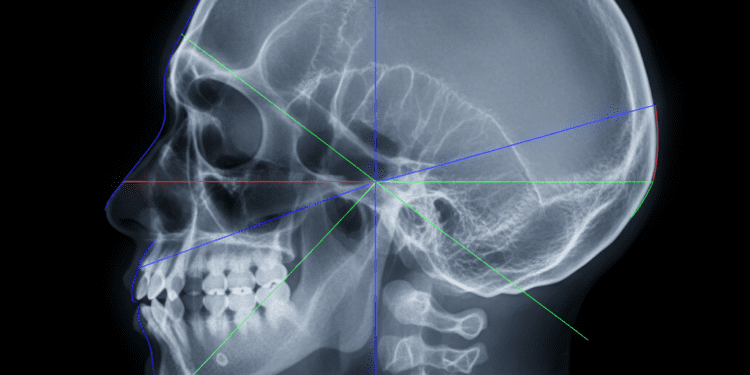

Na prática da radiologia, o posicionamento adequado do paciente é fundamental para garantir a qualidade das imagens e a precisão no diagnóstico. Entre as várias linhas anatômicas que orientam esse posicionamento, duas se destacam: a linha de Camper e a linha infra-orbitomeatal. Neste artigo, vamos explorar essas linhas, suas aplicações práticas e como elas influenciam os resultados radiológicos, trazendo segurança e confiança aos profissionais da saúde.

As linhas de posicionamento facial são referências anatômicas que ajudam a alinhar o paciente de maneira correta durante os exames de radiografia. Essas referências são essenciais para a obtenção de imagens de qualidade e para a diminuição de distorções. Dentre as linhas mais utilizadas estão a linha de Camper e a linha infra-orbitomeatal, que servem como guias para o posicionamento da cabeça e do rosto.

A linha de Camper ou plano de Camper é criada ao se traçar uma linha imaginária que vai da borda inferior do nariz até a borda superior da orelha. Essa linha é utilizada para definir a posição da cabeça do paciente durante o posicionamento em radiografias crânio-faciais.

Na prática, a linha de Camper é utilizada em radiografias como a panorâmica e a cefalométrica. Em uma radiografia panorâmica, por exemplo, a correta inclinação da cabeça do paciente deve estar em harmonia com essa linha, garantindo que todas as estruturas relevantes sejam devidamente capturadas.

A linha infra-orbitomeatal é outra referência essencial, que conecta o ponto infra-orbital (abaixo do olho) ao meato acústico (uma parte do ouvido). Semelhante à linha de Camper, a infra-orbitomeatal serve para alinhar a cabeça do paciente, especialmente nas images do Crânio.

Esta linha é particularmente importante para o posicionamento em exames como a radiografia de seios paranasais e a tomografia computadorizada. Ao seguir essa linha, é possível garantir que o que está sendo analisado esteja em uma posição ideal, contribuindo para diagnósticos mais precisos.